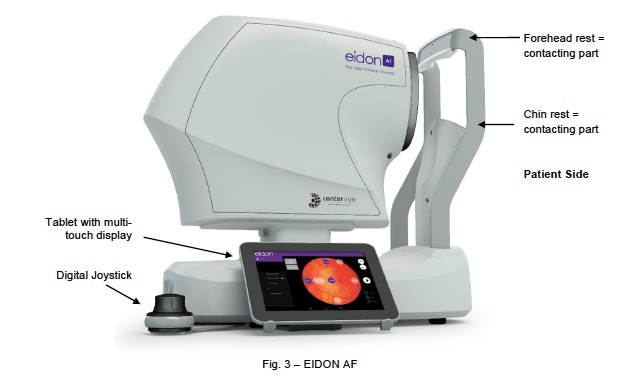

Eidon user manual / Manuel de l'Eidon / Eidon manuale

(CenterVue) Click :Beyond the limits of the device / Au delà des limites de l'appareil / Per oltre i limiti della macchina

2) Autofluorescence with small pupil : 1.64mm